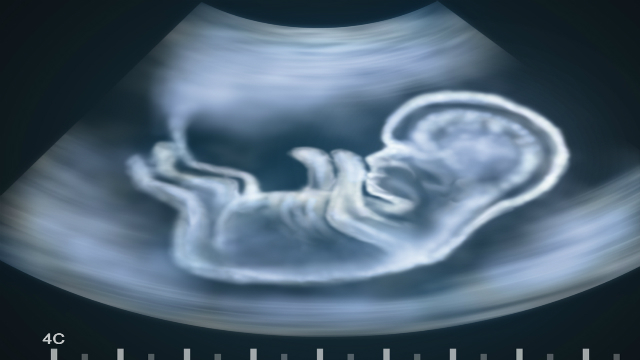

Women’s rights, especially around the issue of abortion, are often a zero-sum political game. Those who oppose abortion tend to oppose it absolutely, viewing the “right” to an abortion as legally sanctioned homicide. Those who view abortion as a women’s rights issue believe that the state has no right to intervene in the private, personal matter of reproduction. This impasse is the cause of endless legislative battles, some direct, others more insidious. In the latter category falls recent legislation in many states that would require women to undergo a medically unnecessary transvaginal ultrasound before being approved for an abortion.

Feldt describes this as part of a new generation of “anti-woman legislation” that seeks “to intrude upon the physician, patient relationship and to make women go through shaming procedures before they’re able to get an abortion.”

Image credit: Alex Mit/Shutterstock.com